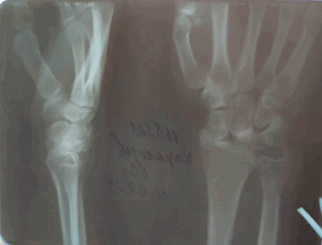

Трансладьевидно-перилунарный вывих запястья III-его типа

Трансладьевидно-перилунарный вывих запястья (перелом ладьевидной кости в виде основной сагиттальной линии, с образованием двух сильно смещенных фрагментов; проксимальный фрагмент остается в нормальном соотношении с полулунной костью; разъединение костей первого и второго ряда запястья).

Наличие мелких костных фрагментов вокруг трехгранной кости вместе с отрывными переломами; смещение кзади трехгранной кости.

Оскольчатый перелом шиловидного отростка лучевой кости.

Локтевая кость цела.